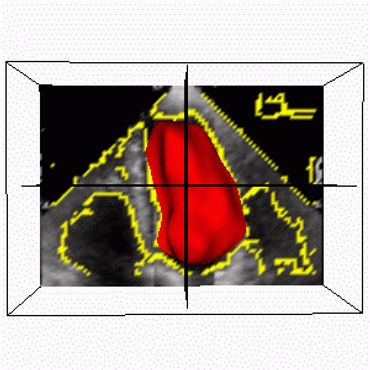

Procesamiento de Imágenes Vectoriales y 4D MRI - Medical Image Analysis (MIA99) (pdf)

DescargarEcocardiografía 3D+T- Transactions on Medical Imaging (TMI02) (pdf)

TODOS LOS CÁLCULOS, IMÁGENES Y ANIMACIONES en esta página y artículos, fueron producidos con PROGRAMAS ESCRITOS POR MI en C / C++ y VTK/TCL/TK

Imagenología Médica del Corazón y Neurociencias

Resonancia Magnética Nuclear ( NMR / MRI )

Ultrasonido / Ecocardiografía 3D ( 3D ECHO )